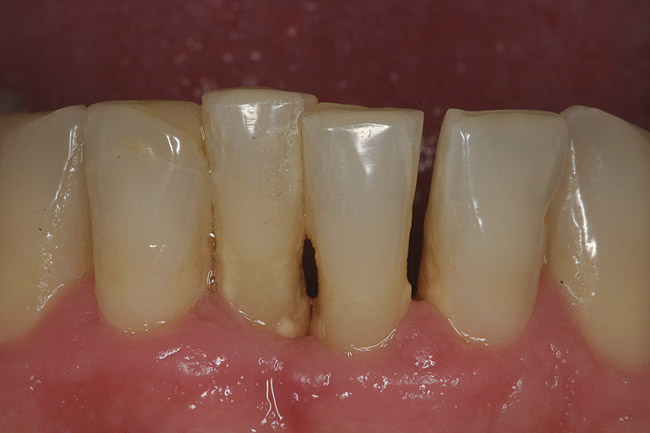

A 53-year-old male presented with localized advanced periodontal disease of the mandibular incisors. Teeth Nos. 23 to 26 exhibited Class II mobility because of advanced bone loss (Figure 1). The teeth had migrated out of position over the years, and a diastema had developed between No. 24 and No. 25 (Figure 2). The patient complained about the poor esthetic appearance of these teeth, and he was able to perceive their loss of strength on function as a result of their mobility.

Figure 1  Preoperative clinical condition.

Figure 1